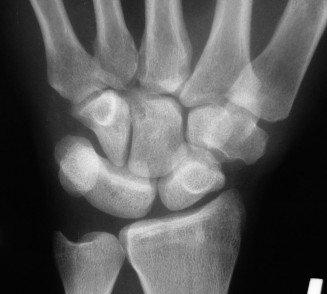

Standard posteroanterior (PA) and lateral radiographs of the wrist often fail to adequately visualize the pisotriquetral joint due to bony overlap from the distal pole of the scaphoid, the capitate, and the triquetrum itself. To properly assess this articulation, a 30-degree supinated AP view (the pisotriquetral view) is mandatory. In our first patient (referencing the classic Figure 3-10), this specific view reveals profound joint space narrowing, subchondral sclerosis, and prominent osteophyte formation at the pisotriquetral interface.

It is crucial to understand the osteology here. The pisiform is an atavistic, sesamoid bone. It is the only carpal bone that does not participate in the complex intercarpal kinematics of the proximal or distal rows. Instead, it lies entirely within the tendon of the flexor carpi ulnaris (FCU). The FCU-pisiform complex extends distally via robust ligamentous attachments: the pisotriquetral ligament, the pisohamate ligament, and the piso-5th metacarpal ligament. Notably, there is no piso-scaphoid ligament; the scaphoid resides on the entirely opposite side of the carpus.